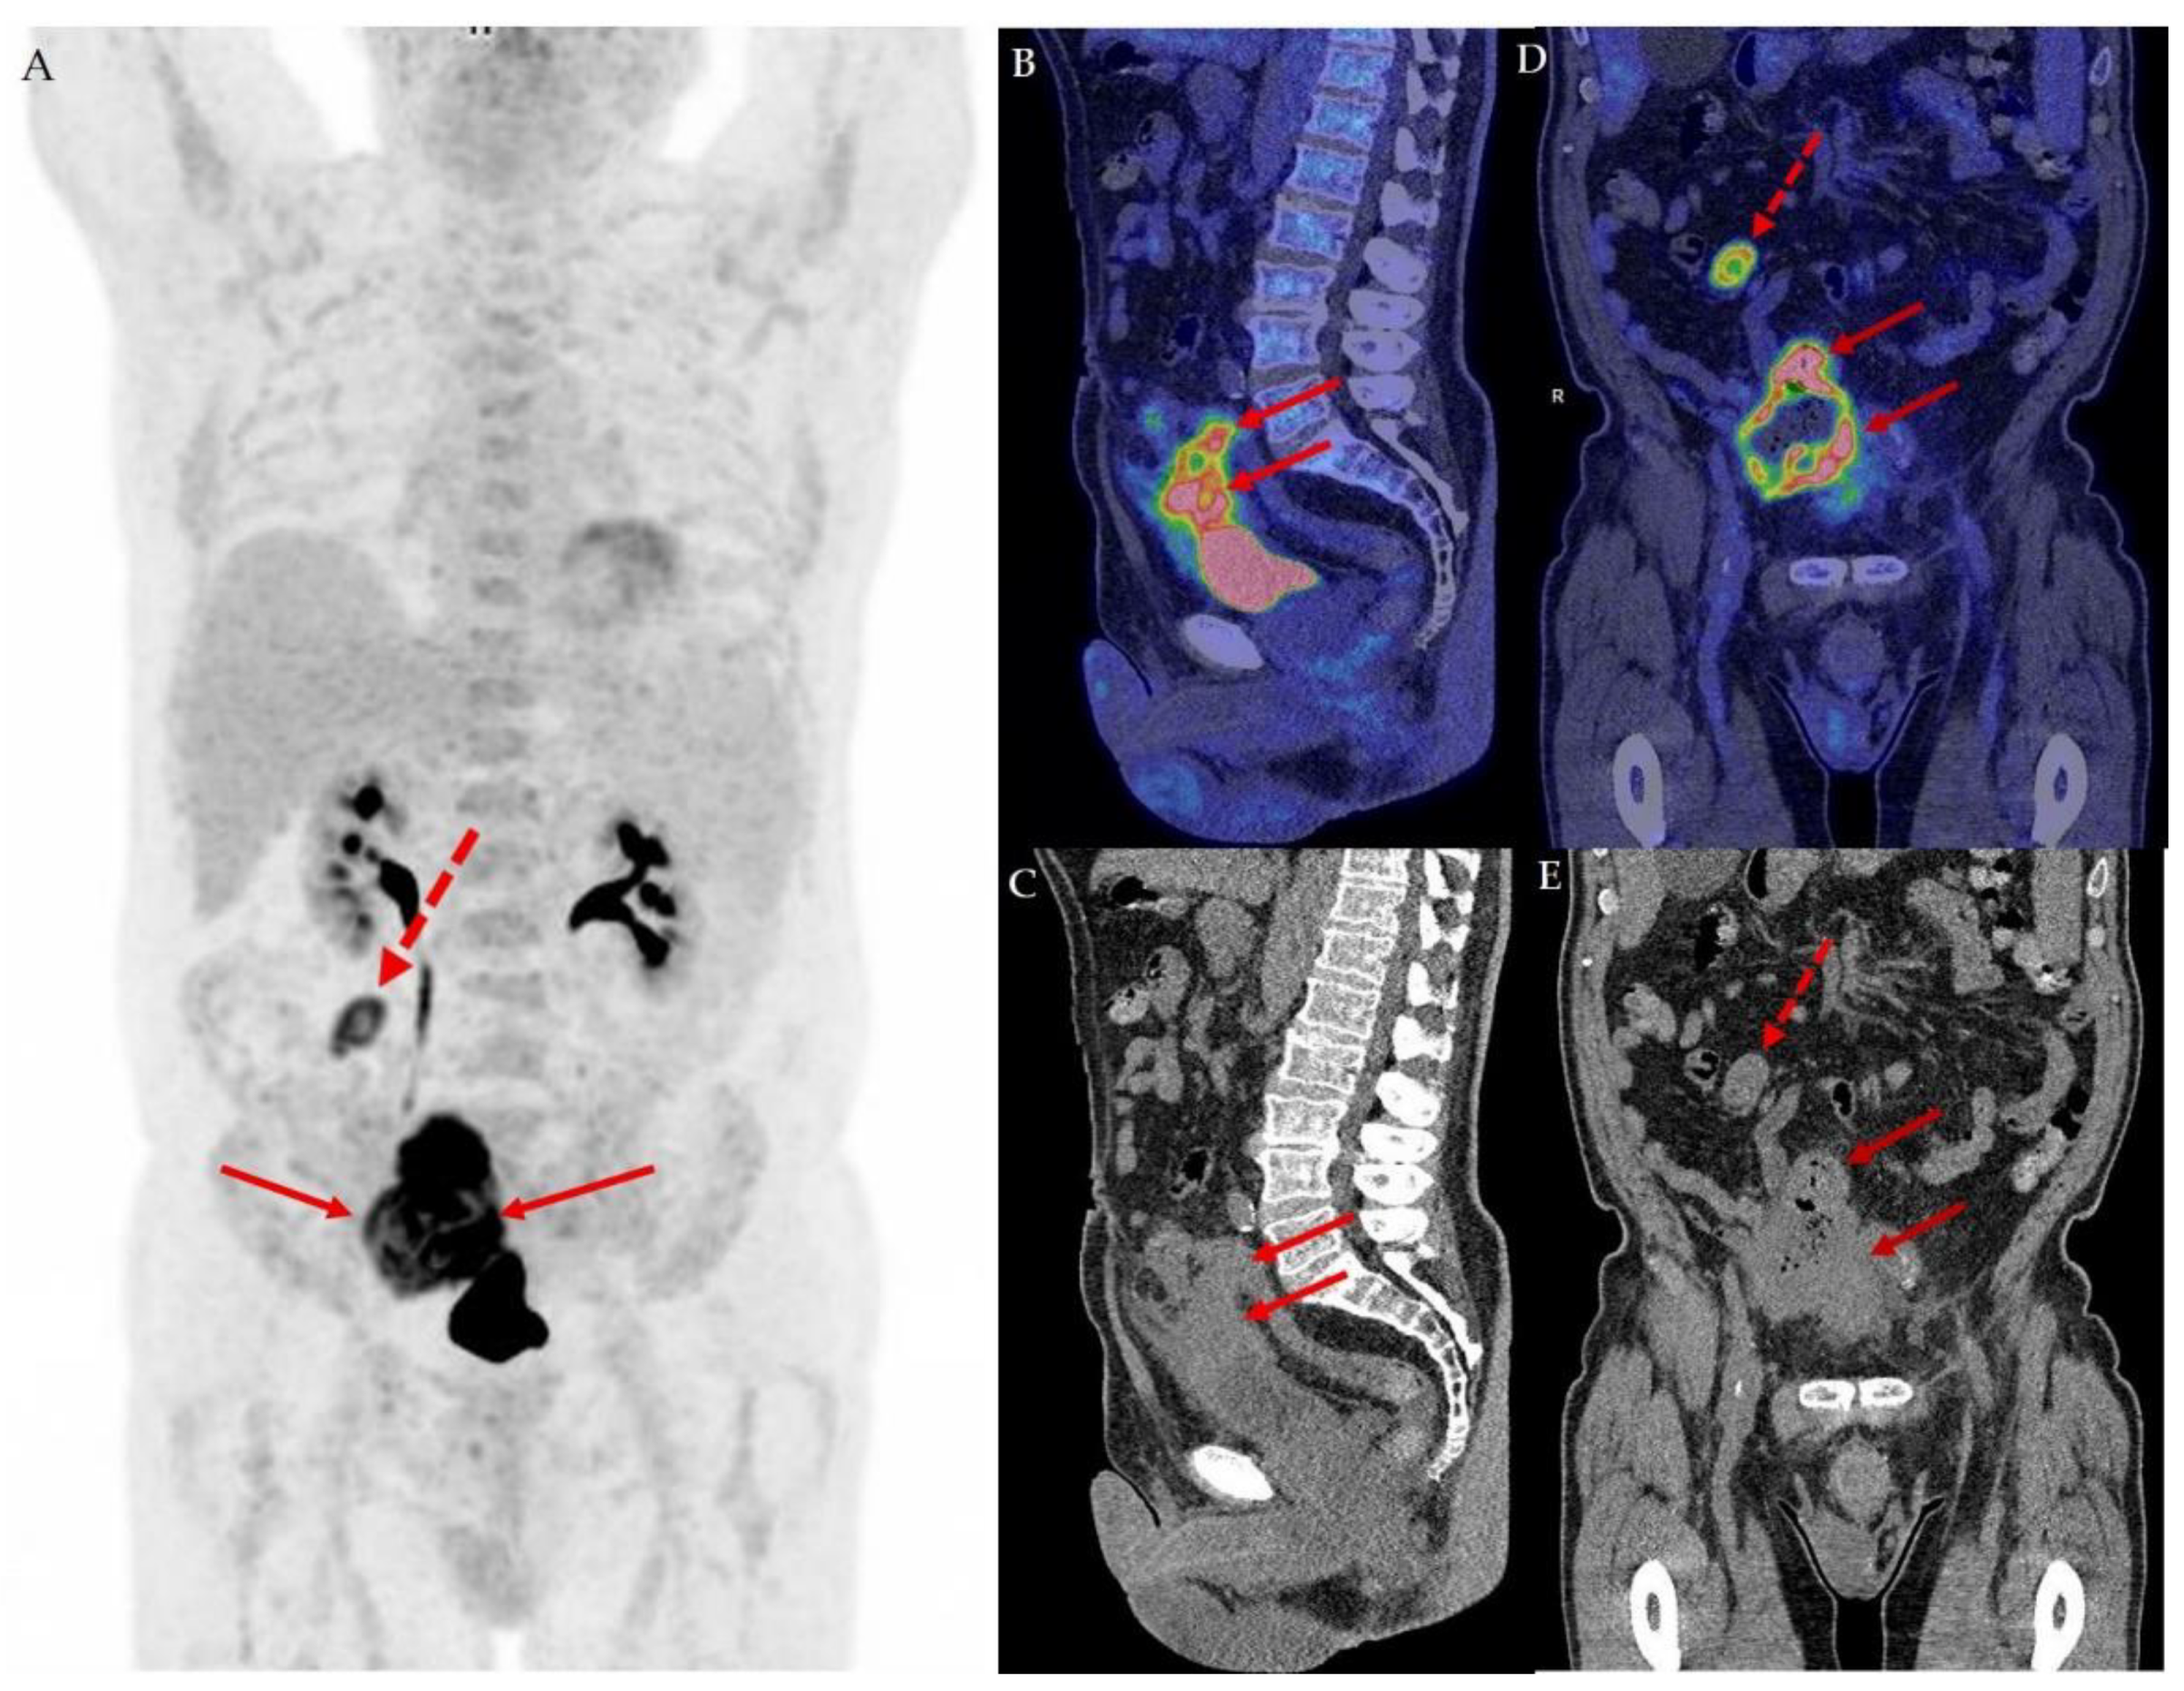

We present a 76-year-old man initially suspected to have an advanced colon cancer infiltrating nearby organs including the bladder and small intestines. During colonoscopy, the operator describes an ulcerating tumor in the sigmoid colon occupying more than half of the circumference. Surprisingly, the biopsies revealed a urothelial carcinoma. A supplemental 18F-FDG PET/CT conducted as part of the Danish standard-of-care for staging of muscle invasive bladder cancer was conducted along with a cystoscopy [1,2]. The maximum intensity projection of the 18F-FDG PET/CT image in the anterior view (A) revealed a high tracer uptake in an infiltrating tumorous mass coherent with the top of the bladder (full arrows) and an enlarged metastatic lymph node with high tracer uptake (dotted red arrow) in the upper right abdomen. In the sagittal view of the fused 18F-FDG PET/CT image (B) and low-dose CT (C), the coherence of the tumor to the top of the bladder wall stretching along the urachus is elegantly illustrated, supporting the suspicion of a urachal cancer. The tumor infiltrates the peritoneum, small intestines and sigmoid colon. The intestinal involvement is apparent in the coronal fused 18F-FDG PET/CT image (D) and coronal low dose CT (E), which shows the tumor (full arrows) and lymph node metastasis (dotted arrow). The cystoscopy revealed no visible tumors and a normal bladder wall. However, a small area in the top of the anterior bladder wall looked edematous. A small transurethral resection of 3 ml tissue from this area fulfilled the criteria for the diagnosis of urothelial carcinoma, high-grade, originating from the urachus, except that no urachus remnants were found in the specimen [3]. The stage according to the Sheldon Classification [4] was IVA and according to the TNM 8th Edition [5] and TNM Supplement 5th Edition [6] pT4a.